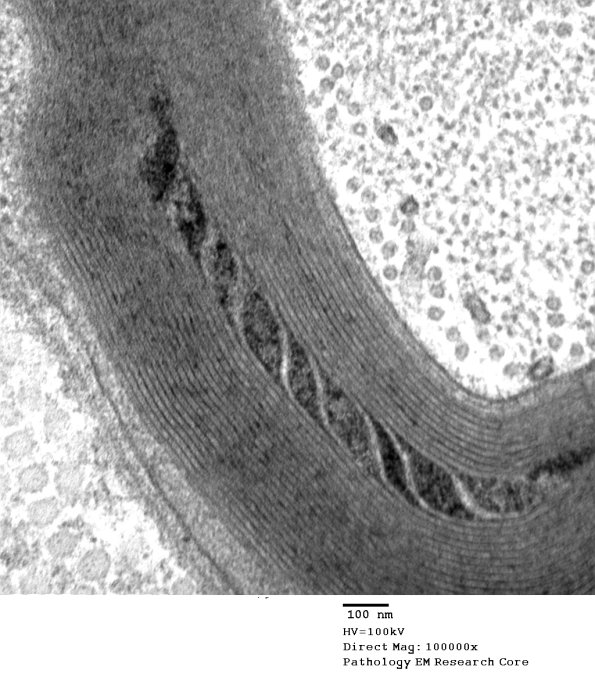

Higher magnification of image #7B1. (electron micrograph)